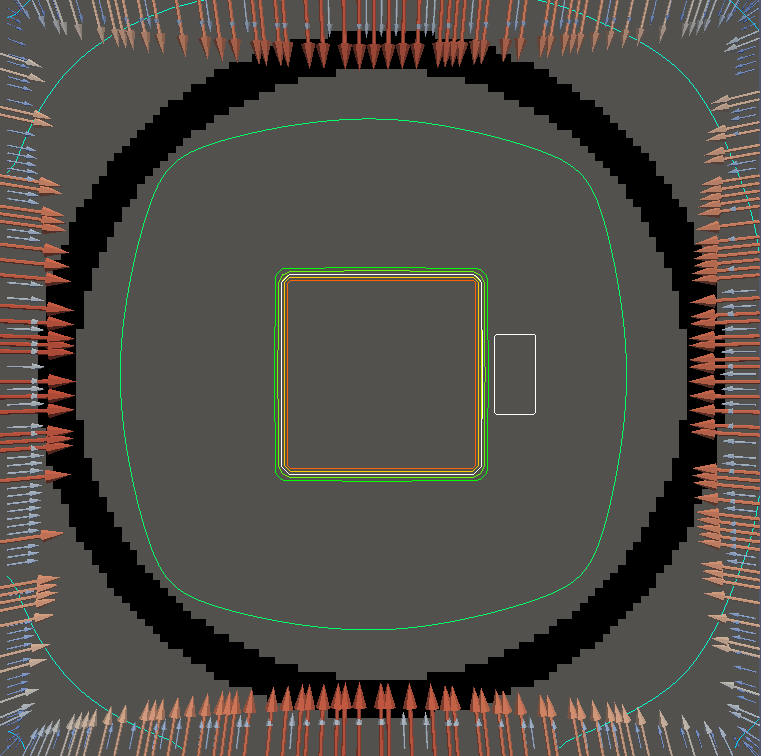

For testing, we use three tumor/risk region regions similar to those in [13]. Specifically, we define the regions in Table 3 and are shown in Figure 1; the void region is shown in black and the tumor and risk regions are traced in white. In the basic target case, seen in Figure 1(a), the tumor region is a box, as is the risk region. The second, intermediate target case, seen in Figure 1(b), involves an L-shaped tumor around a box-shaped risk region. Finally, the complex target case in Figure 1(c) involves a C-shaped tumor around a risk region.

Figure 2 shows the optimal boundary source term for both and The vectors shown on the boundary are the time-integrated values of normalized and then scaled by In Figures 2(a), 2(c), and 2(e) (corresponding to ), the isolines are spaced at intervals of the maximum of the desired dose (here, 5). In the intermediate and tracking cases, we see that relatively low dose levels are attained, primarily due to the high penalty to any dose deposited in the risk region. In Figures 2(b), 2(d), and 2(f)(corresponding to ), the isolines are spaced at intervals of of cells killed. Here a high proportion of the tumor cells are killed (in each case ) while in the Intermediate and Basic cases, the tumor has at least survival; in the Complex case, the risk region has survival.

We conclude with a final set of numerical examples which restrict the location of the source by altering the definition of Here we require that on one side of the boundary. For the basic and intermediate case, we require that the external source not come from the left side of For the complex case, we disallow sources on the right side (as the optimal source is nearly zero on the right side in the complex case for ). Figure 4 shows the optimal solution for both problems, using the same penalization parameters used in Figure 2. The optimal dose for is significantly worse, with the tumor in the intermediate and complex cases getting a dose below However, the tumor cells have a survival of or less for each case and the risk region has a survival rate of or higher in each case.